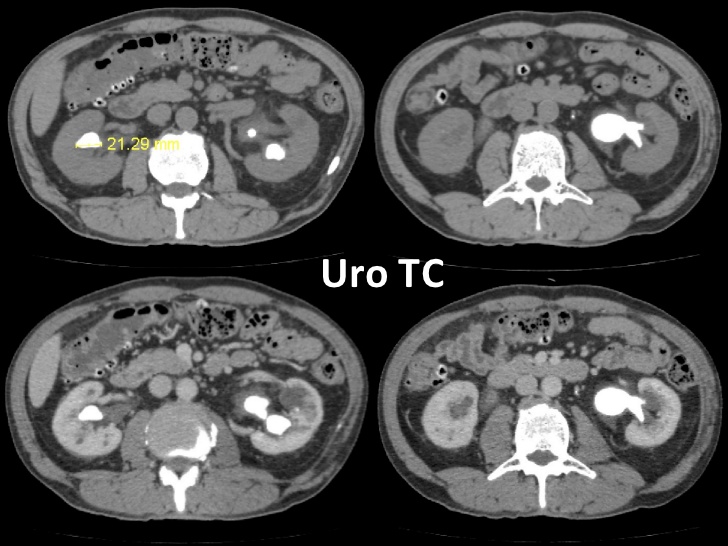

La URO-CT es una técnica diagnóstica optimizada para visualizar riñones, uréteres y vejiga mediante su examen con cortes finos (con TCMD), con la administración de contraste iodado y adquisición de imágenes en la fase excretora renal.

El problema básico radica en la obtención en varias fases – barridos, ya que el URO-TC clásico: consta de 4 fases:

Fase sin contraste (abdomen-pelvis): búsqueda de litiasis. Se debe comparar el realce de lesiones.

Fase córtico-medular: sólo riñones 35-40

Fase nefrográfica (sólo riñones, 90´´ aproximadamente), posee la mayor sensibilidad para detectar masas renales y comparar realce inequívoco tras la administración de contraste.

Fase excretora (abdomen-pelvis): realizada 5-15 minutos desde la inyección del contraste. Para evaluar el urotelio.

En la actualidad ya se realiza el protocolo de UROTC-Split bolus de contraste, ya que implica menor dosis de radiación, este protocolo consiste en solo dos fases:

1. Fase sin contraste (baja dosis/dosis ultra baja)

2. Fase mixta nefrográfica-excretora.